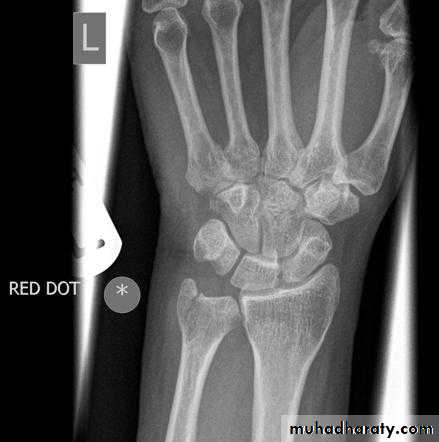

• عمليا يتم تصوير الرسغ والمرفق والكتف لمن يبدوا ظاهرا دون سن العشرين عاما من العمر. ويصور الحرقف لمن بدا في اواسط العقد الثالث من العمر او اقل, والنهاية الانسية للترقوة والتحام القص بالرهابة لمن تجاوز ذلك.

53• معدل ظهور والتحام المراكز التعظمية تبعا للعمر:

• 3) في نهاية السنة الرابعة يظهر متع لرأس الكعبرة.

• 4) وفي بداية السنة الخامسة يظهر متع للعظم المربع المنحرف وفي نهاية السنة االخامسة يظهر المركز التعظمي لعظمي شبه المنحرف والزورقي الرسغيين.

• 5) في سن السادسة يظهر متع للقمة الانسية لعظم العضد والنهاية السفلية لعظم الزند.

7) في نهاية السنة التاسعة يظهر متع للنتوء المرفقي لعظم الزند والعظم الحمصي.

8) في نهاية السنة العاشرة يظهر متع اللقمة الوحشية للعضد.